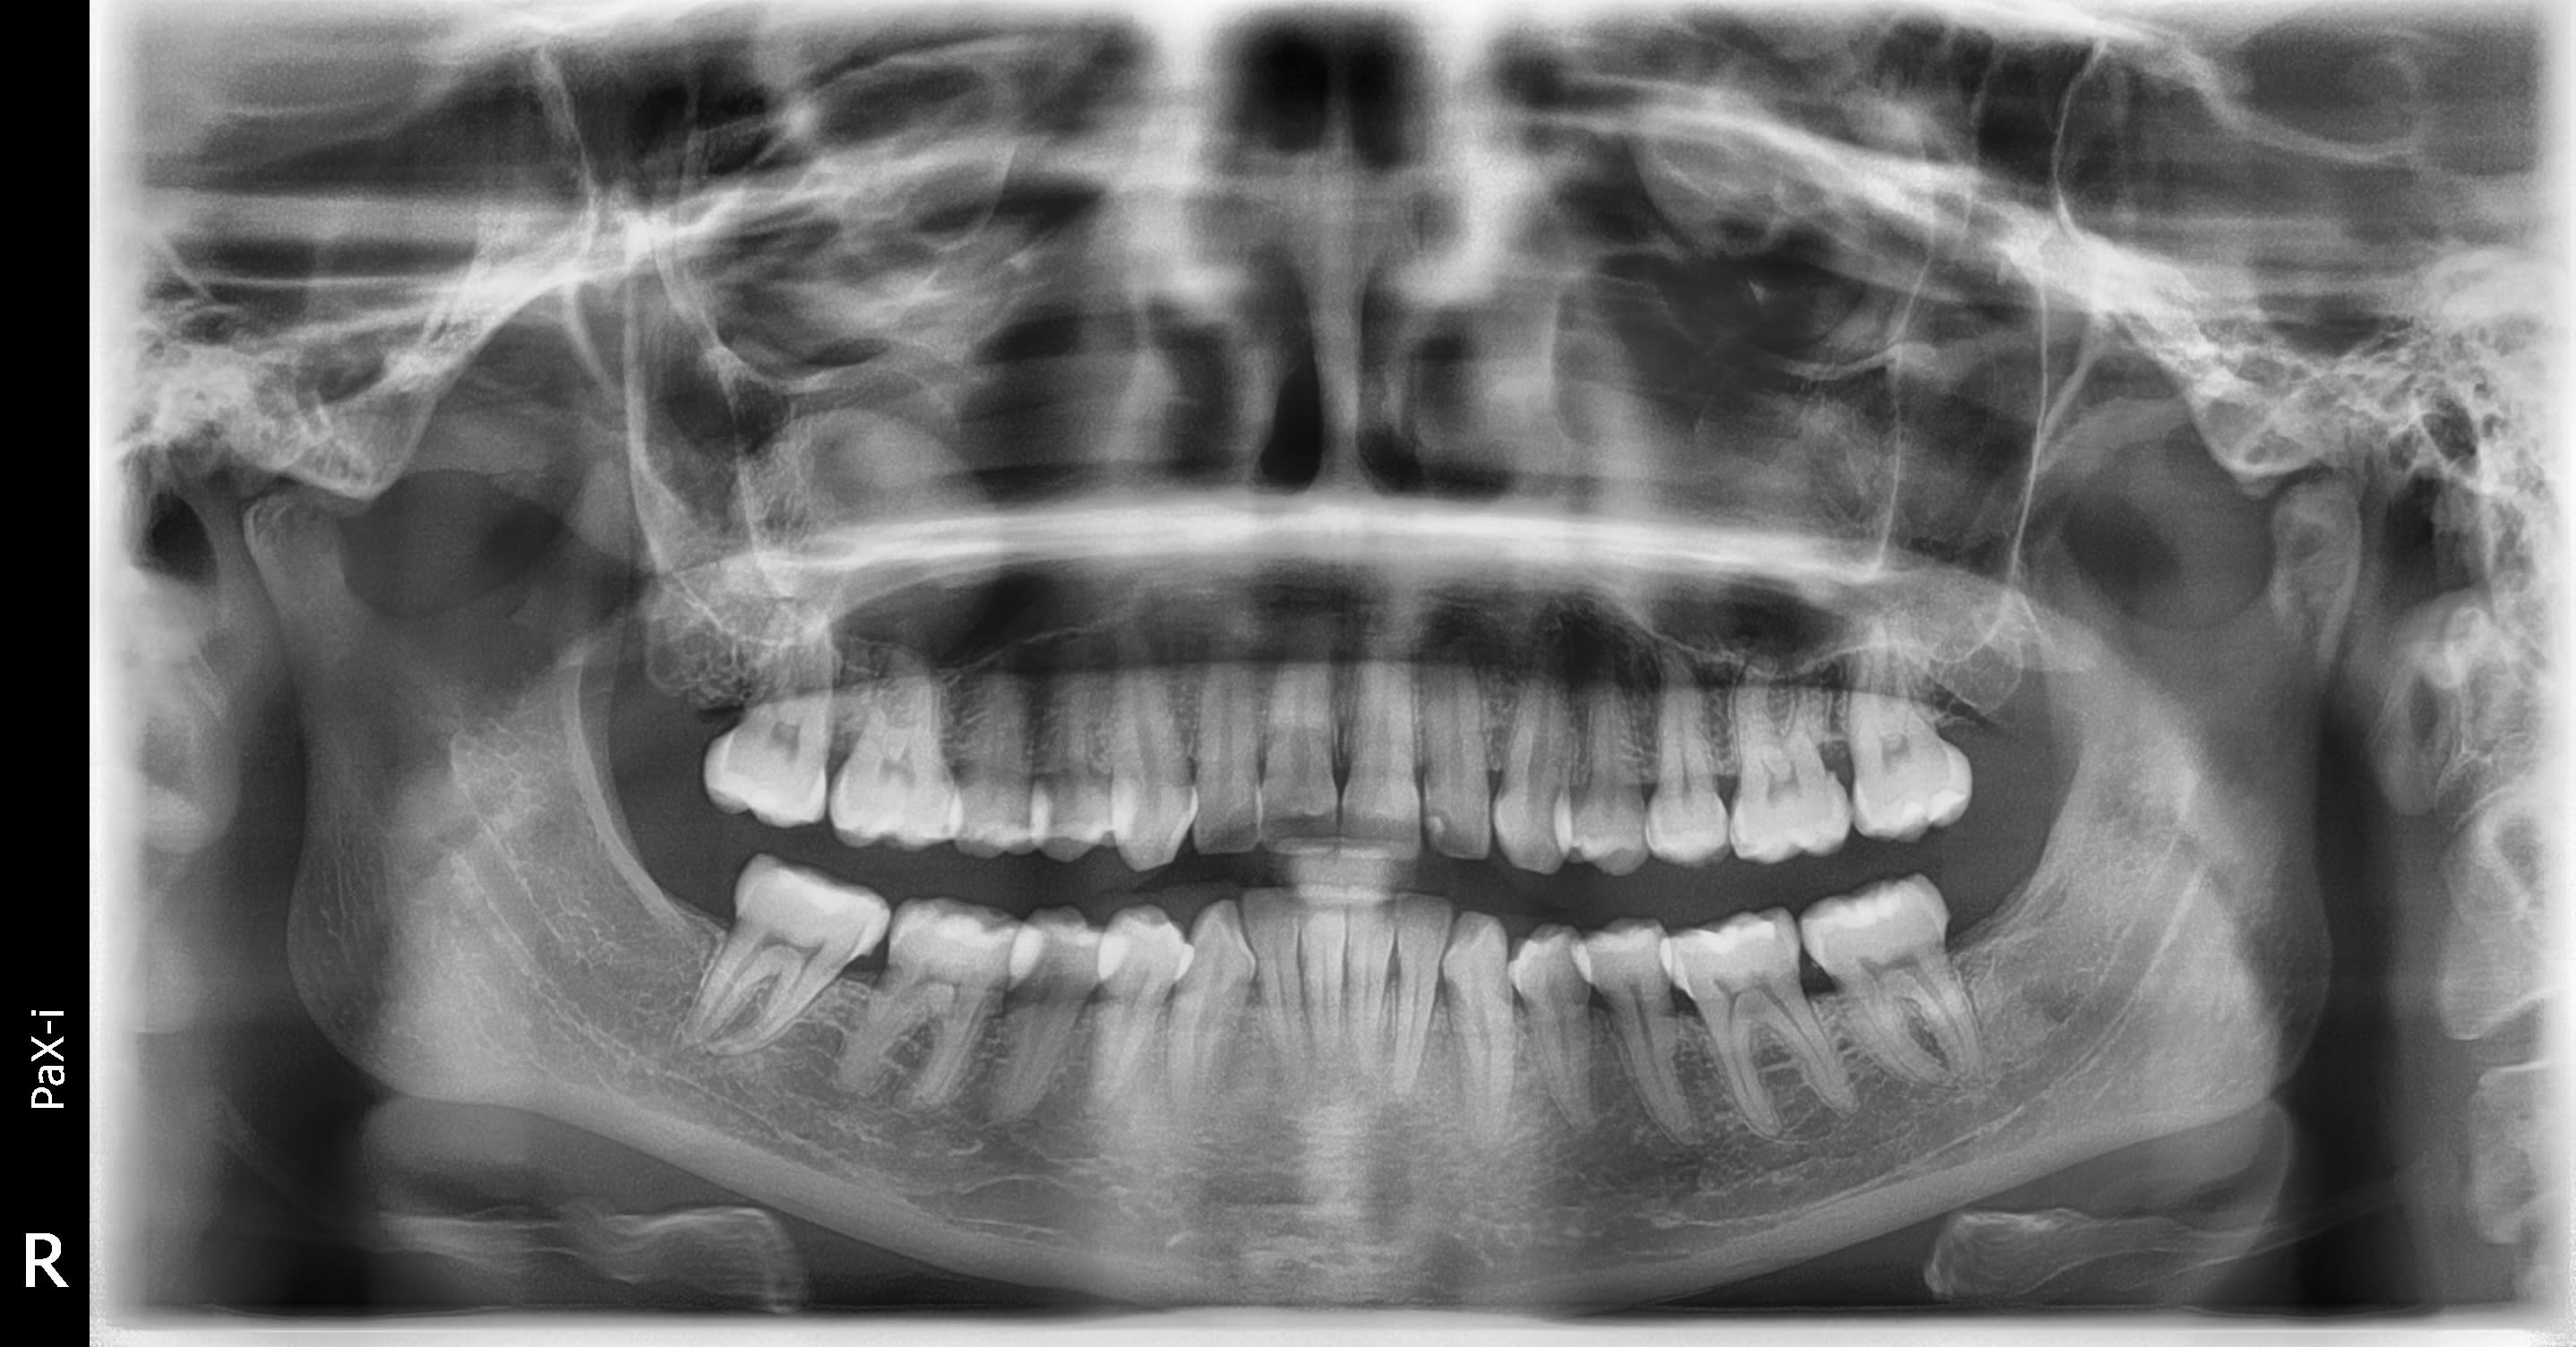

J'ai un doute sur le sinus droit, vous en pensez quoi ?

Je compte adresser à l'ORL.

Pas de douleur, pas fumeuse, 30 ans, en bonne santé.

Pour moi il s'agit d'un artéfact.

Cela me semble aussi bien géométrique mais la patiente n'avait pas de collier ni de boucles d'oreilles !

des opacités sinusiennes asymptomatiques, non pathologiques, se voient dans 20 % de la population ; il s’agit volontiers de simples kystes sous-muqueux, d’étiologie mal élucidée, retrouvés volontiers en cas de trouble de la ventilation sinusienne par rétrécissement ou obstruction ostiale et/ou encas de pathologie dentaire sous-jacente; leur contenu est muqueux ou séreux (Fig.2c) et ils sont souvent faussement décrit comme des « polypes », le cone beam comme le scanner ne pouvant les distinguer; dans le doute, l’endoscopie tranche.

Pas de symptomes, pas de dents suspectes, forme reguliere, pas de lyse osseuse, pas de formation osseuse autour => pas de problemes, on verifie de temps en temps pour voir l'evolution.